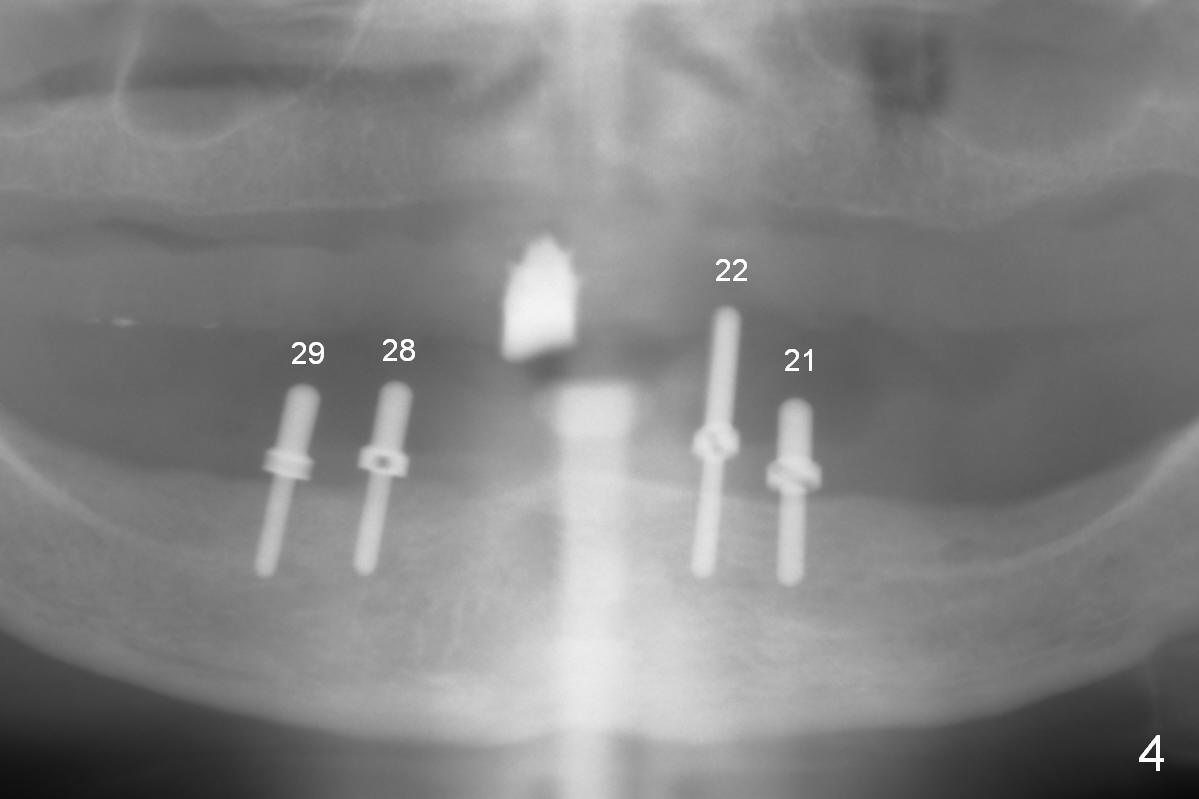

Preop photo shows that the lower lip is protrusive (Fig.1), because the lower complete denture (CD) is in cross bite (Fig.3). When the upper and lower CDs are removed, the upper and lower lips are retrusive (Fig.2). Use a modified CT scan stent to start osteotomies at the sites of the canine and the 1st premolar (Fig.4). In fact the right ones are more distal than planned. As expected, four of 3.8x8 mm implants are placed with insertion of 3.9 mm ball abutments with 2 mm cuff (Fig.5). The lingual plate at the site of #21 perforates apically when a 2.7 mm drill is being used. The defect is repaired with collagen plug and autogenous bone and Osteogen prior to implant placement. There is no postop sublingual edema or paresthesia. With trimming of the lower CD (especially the posterior border), the four implants/ball abutments appear to help establish normal overjet with immediate improvement of the facial profile (Fig.6,7 (3 days postop)). The border of the denture flange is trimmed (Fig.7 black *) to avoid contacting the tender hyperplastic tissue (white *). Further trimming may be necessary, which has been accomplished. A month later, three more implants are placed in the mandible.